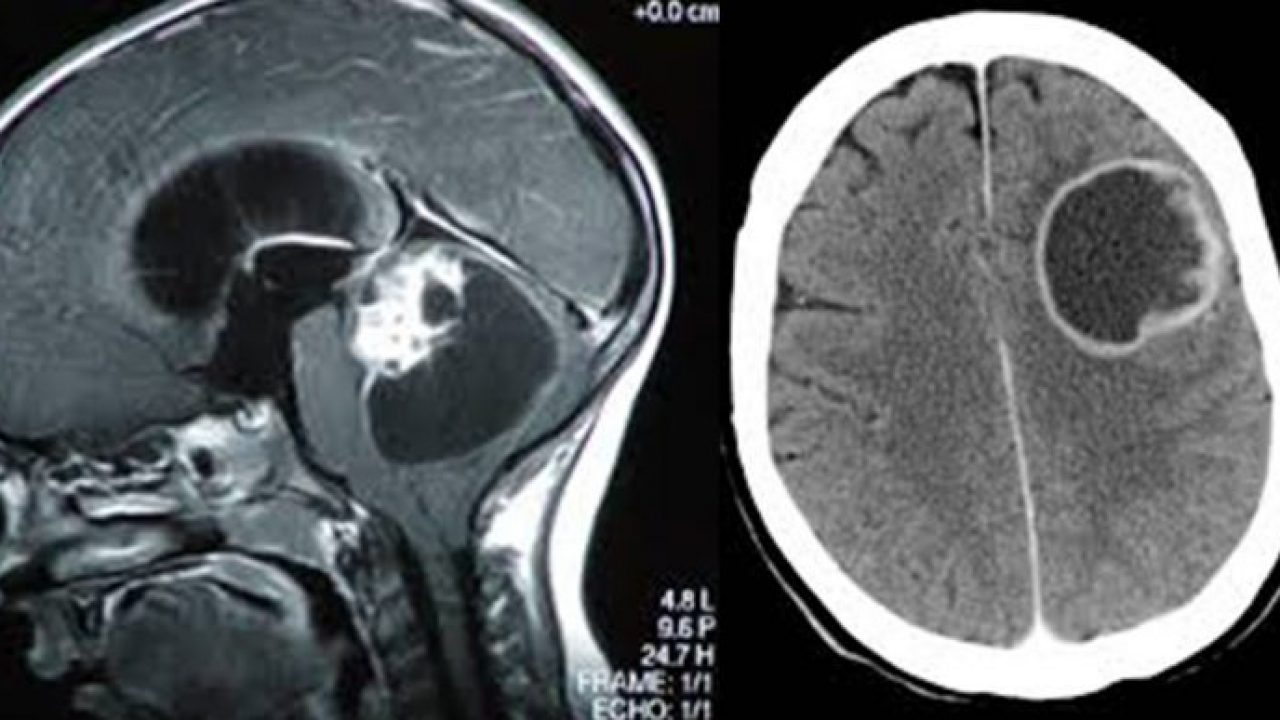

Tumore Al Cervello Sintomi Diagnosi E Cure

Tumore Al Cervello

Tumore Del Cervello Malattie Oncologia Pazienti It

Tumore Cerebrale Wikipedia

Tumore Al Cervello Sintomi Cause E Sopravvivenza

Tumore Al Cervello Sintomi Iniziali E Tardivi Sopravvivenza Aspettativa Di Vita Medicina Online